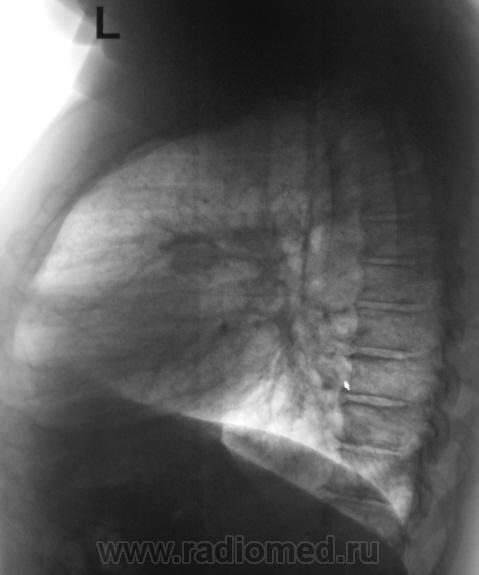

2. Конечно, мы на свой страх и риск, произвели дообследование, согласно стандарту. Итог дообследования представлен в серии 3.

Великолепный материал, огромное спасибо! И поучительно, и вся динамика представлена

Как говорят в Одессе - "Вы сильно не правы!"

Было сказано, что "У Вас ничего нет, Вам просто надо бросить курить". НА УЧЕТ ПАЦИЕНТ НЕ ПОСТАВЛЕН, ДИАГНОЗ ТАКЖЕ НЕ ПОСТАВЛЕН.

Все признаки периферического рака...."расти" так может и лет пять...пока репу в диспансере будут чесать...

"Ошибаются везде, и сельской амбулатории, и в крупных центрах. Вы в заключении написали "периферический рак"?"

В заключении, именно однозначно, выставлен данный диагноз, изображения и все необходимое записано на диск. Это не ошибка для ООД. В ООД такой ошибки быть не может, ибо это специализированное учреждение.  Кстати, это, как Вы понимаете, случай не единичный.